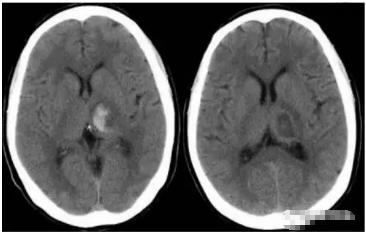

二、丘脑出血:

如属一侧丘脑出血,且出血量较少时,表现对侧轻瘫,对侧偏身感觉障碍,特别是本体感觉障碍明显。如果出血量大,受损部位波及对侧丘脑及丘脑下部,则出现呕吐咖啡样物,呕吐频繁呈喷射状,且有多尿、尿糖、四肢瘫痪、双眼向鼻尖注视等症。病情往往危重,预后不好。

左侧丘脑高密度影,边界清晰,周围可见水肿,有占位效应,隔期复查,血肿吸收,呈边界清晰的低密度影。